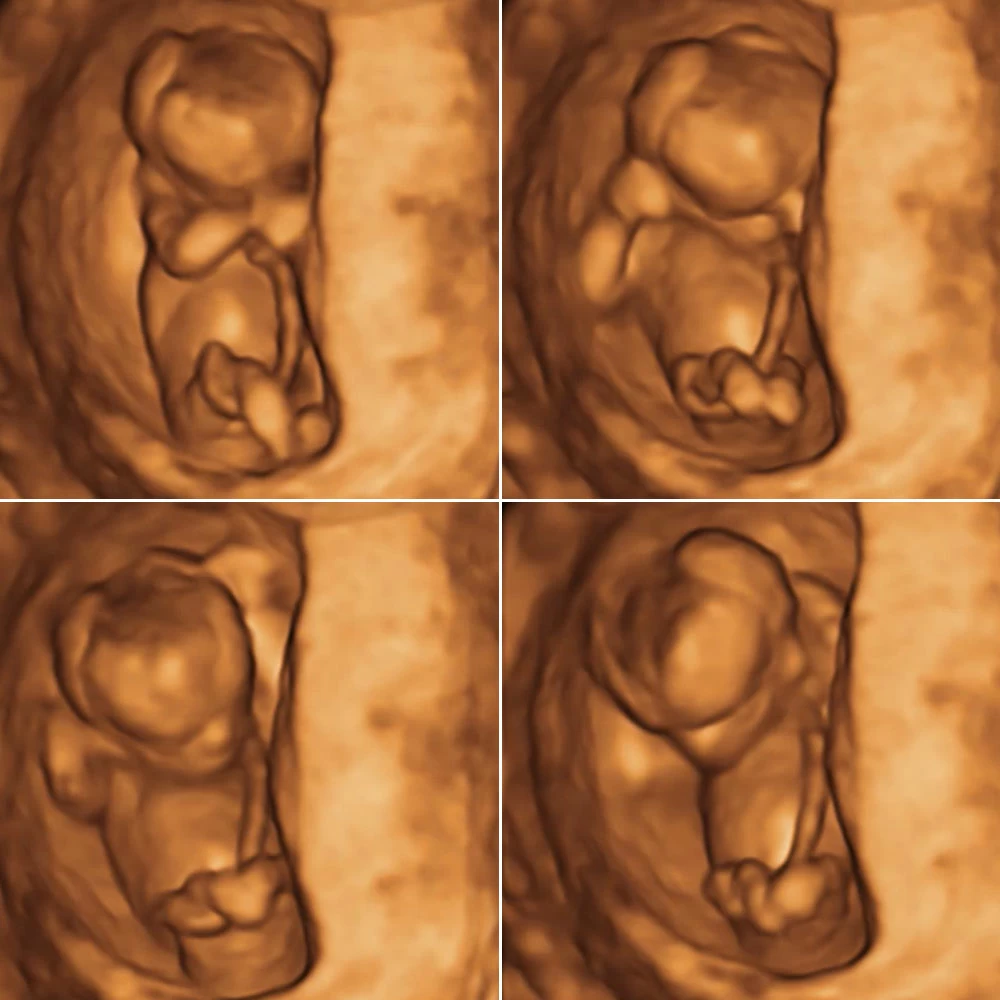

Неделя № 10

К концу десятой недели длина плода от копчика до темени составляет 35-40 мм.

Пропадает имеющийся раньше хвостик. Плод находится в матке достаточно в свободном положении.

Продолжается развитие нервной системы. При прикосновении к стенкам матки ребенок совершает движения в ответ: поворачивает голову, сгибает или разгибает руки и ноги, отталкивается в сторону. Размеры плода еще очень малы, и женщина пока не может ощущать эти шевеления.

Формируется сосательный рефлекс.

Завершается развитие диафрагмы, которая будет принимать активное участие в дыхании.

Неделя № 11

К концу этой недели копчиково-теменной размер плода увеличивается до 4-5 см.

Тело плода остается непропорциональным: мелкое туловище, большие размеры головы, длинные руки и короткие ноги, согнутые во всех суставах и прижатые к животу.

Плацента уже достигла достаточного развития и справляется со своими функциями: обеспечивает поступление к плоду кислорода и питательных веществ и выводит углекислый газ и продукты обмена.

Происходит дальнейшее формирование глаз плода: в это время развивается радужная оболочка, которая в дальнейшем будет определять цвет глаз. Глаза развиты хорошо, полуприкрыты веками или широко открыты.